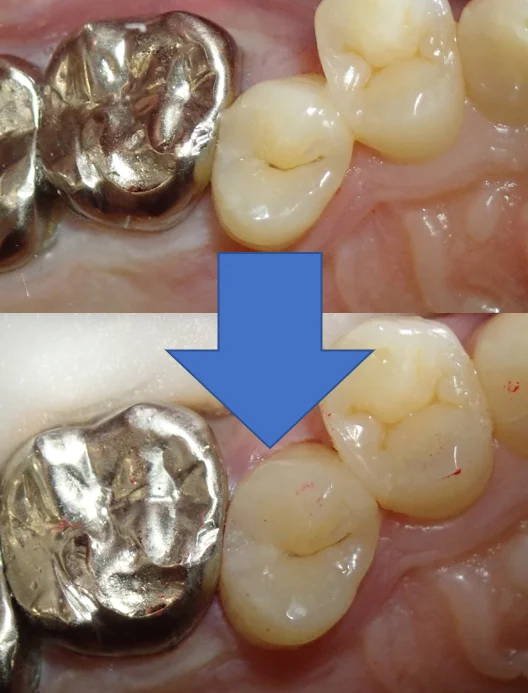

この日の術前術後がこちらです。

で、2日目最終的な術前術後がこちらです。

歯の乾燥の為、まだ色が合っていませんが、1週間くらいすると馴染んできます。

無事に虫歯も取りきり、段差などなく仕上げることが出来たため、良かったです。